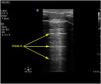

Para esta medición se utiliza una sonda lineal de alta frecuencia, colocada entre los últimos espacios intercostales (colocamos la sonda en la línea axilar anterior perpendicular, por lo general a los espacios intercostales 7°-8°, 8°-9°, y 9°-10° comprendiendo el transductor 2 costillas para visualizar la zona de aposición del diafragma (Supl. fig. 13) con el paciente en supino idealmente. Se ha descrito también una localización de la sonda algo más posterior, entre las líneas axilares anterior y media. De esta forma se localiza la «zona de aposición», donde el diafragma se inserta en la pared costal. El diafragma se identifica como la franja hipoecoica limitada por dos líneas hiperecoicas, que corresponden a la pleura y al peritoneo (Supl. fig. 14)22,31–35.